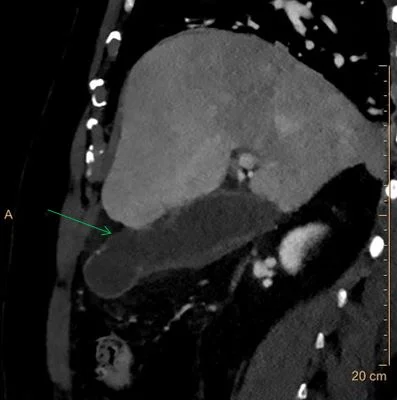

40 keV image: Clear disruption in wall enhancement (green arrow). No negative gallstones are seen.